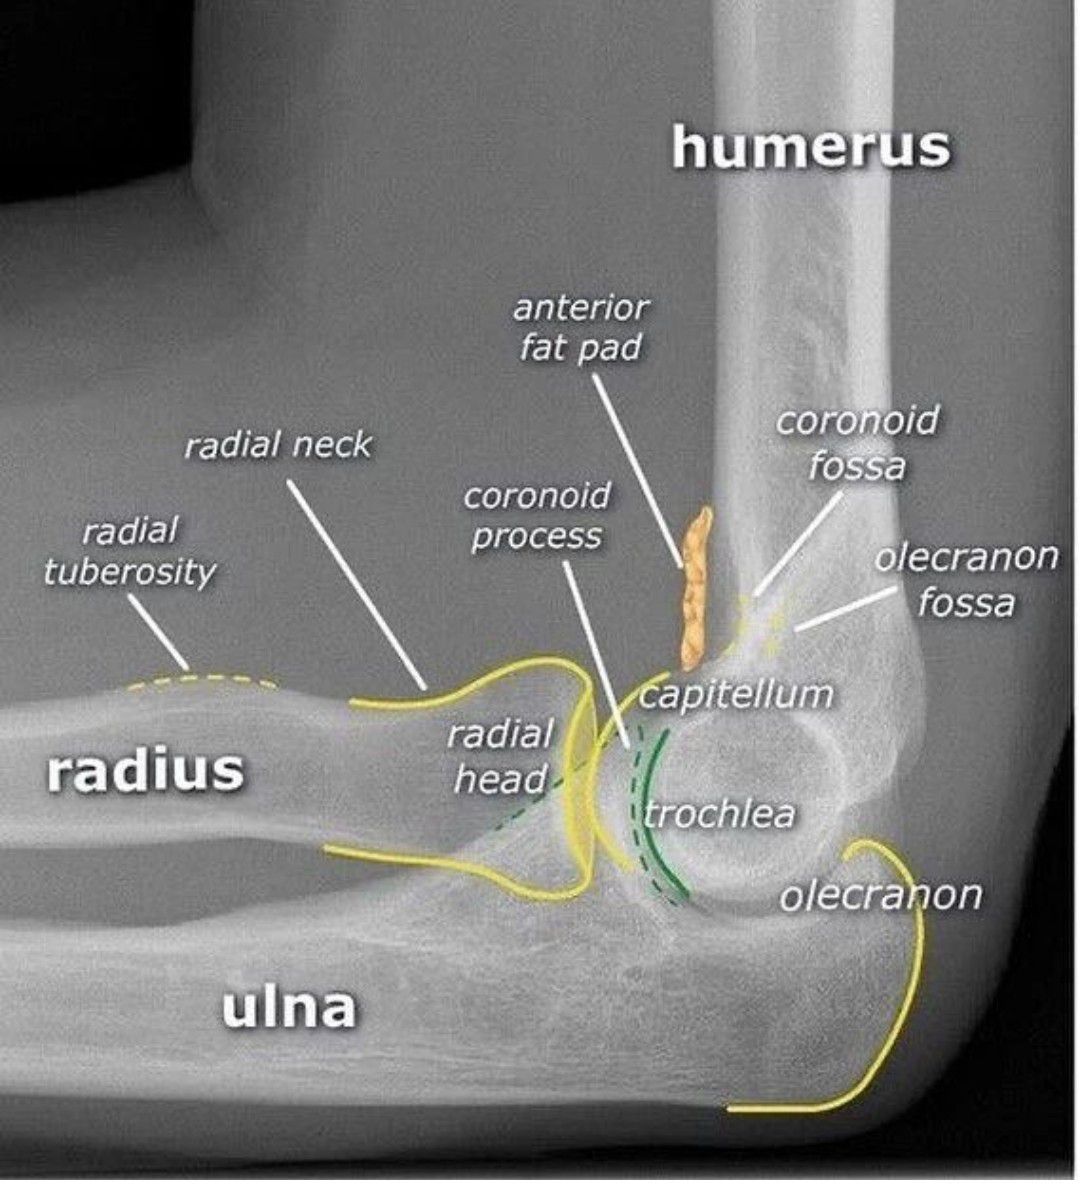

Elbow X-ray Anatomy

Here is a brief radiological review of the elbow.